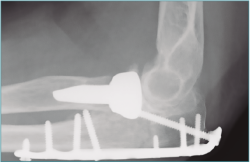

Las pruebas de imagen más útiles en este contexto son la radiografía simple (Figura 3) y la tomografía computarizada (TC) (Figuras 4 y 5), que evalúan la congruencia de las superficies articulares, la presencia de osteofitos u osificación ectópica, o alteraciones de la alineación ósea. Además, se evaluará la consolidación de fracturas previas, si es el caso, o la posible implicación del material de osteosíntesis en la falta de movilidad (si está correctamente situado, no tiene por qué interferir con la movilidad del codo)(6).

Figura 3. Radiografía de paciente con rigidez de codo con presencia de material de osteosíntesis a nivel de cúbito proximal y protésico a nivel de radio proximal.